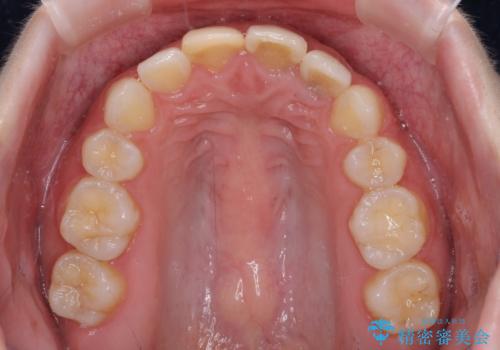

抜歯矯正の後戻り インビザラインによるオープンバイトの再矯正

- 以前矯正治療をされていましたが、後戻りが起きたことを気にして来院された患者様です。

上下前歯のオープンバイトを改善するため、インビザラインにて治療を行うこととしました。